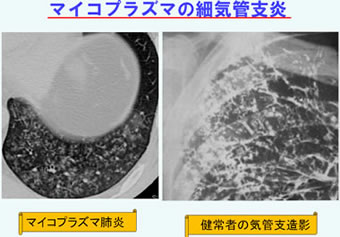

肺炎の画像診断と最新の診療 新型コロナ/富士フイルム、AIで肺炎診断支援 技術開発の詳細情報

新型コロナ/富士フイルム、AIで肺炎診断支援 技術開発。解答・解説】1カ月続く乾性咳嗽を主訴に受診した60歳代女性。肺CT検診 | JR仙台病院。肺がんの診断、特にCTとPET 豊田 尚之 - YouTube。「肺炎の画像診断と最新の診療」藤田次郎定価: ¥ 12,540#藤田次郎 #本 #BOOK #健康 #医学